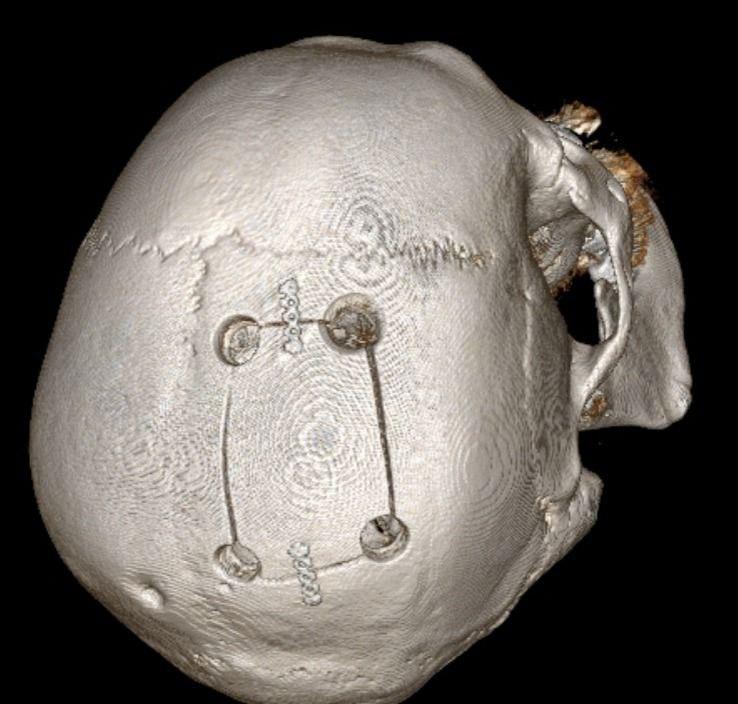

Нейрохирурги выполнили трепанацию черепа и полностью удалили опухоль. Операция завершилась успешно, двигательные функции левой стороны тела у пациента восстановились, а мозг вернулся к своему нормальному положению.

«При удалении опухоли такого большого объема у пациента происходят резкие колебания внутричерепного давления, вызывая смещение ствола головного мозга. А это в свою очередь серьезно влияет на работу сердца и уровень артериального давления вплоть до критических нарушений. Данная ситуация потребовала особого внимания и крайне тяжелой и сложной работы не только нейрохирургов, но и врача, обеспечивающего анестезиологическое пособие операции», — говорит нейрохирург ГКБ Пятигорска Вадим Зотов.